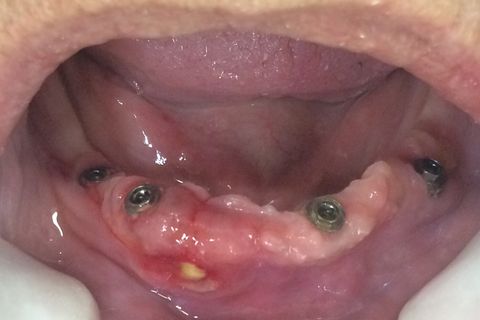

Protese ajustada e parafusada

Dois dias após ajuste

Alivio da dor, melhora do caso em 2 dias

Suspeita inicial era perda de implante mas ao retirar a prótese, foi verificado que os pilares estavam firmes e presença desta ferida.

A ferida se deu por uma base muito extensa sobre a mucosa somado a soltura da prótese.

Foi corrigida a ausência de espaço higiênico e sobreextensão da base.

A ferida que inicialmente estava escondida somente vista sua borda por espelho agora esta livre para cicatrizar.

Protocolo recolocado.